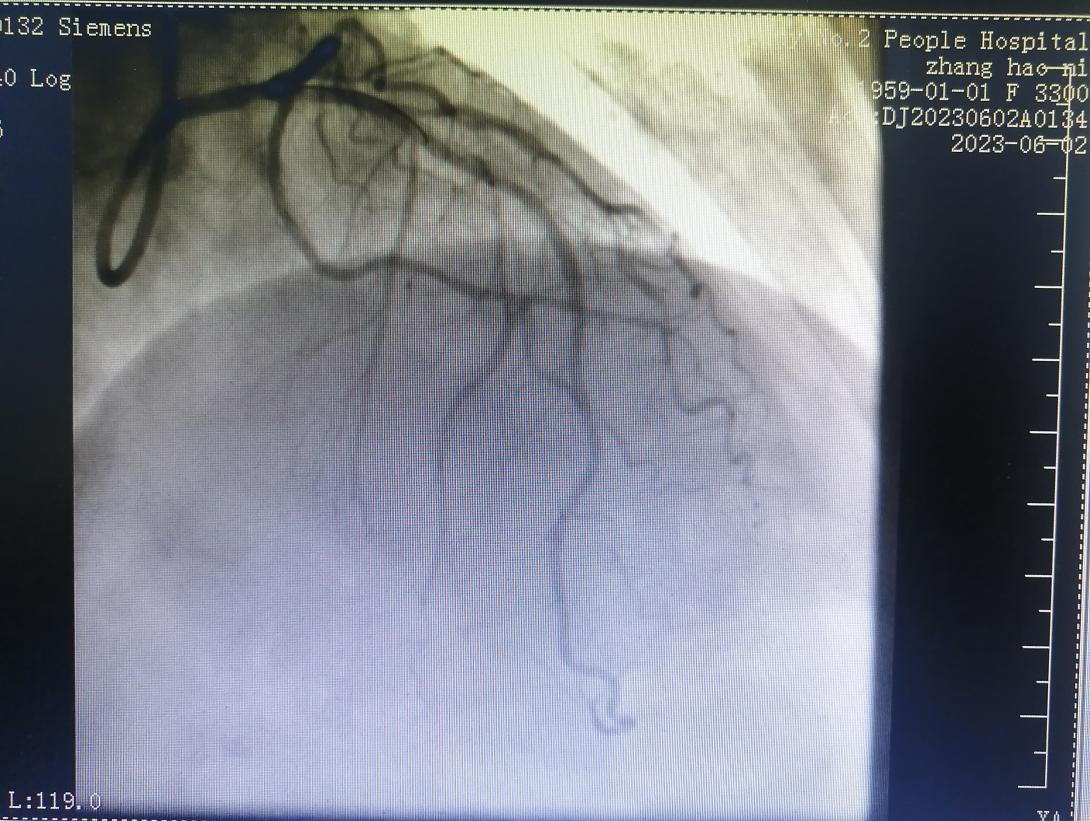

術(shù)前:

術(shù)后:

64歲的張阿姨,因“間斷胸悶3月余,加重5天余”入住心血管內(nèi)科。入院后,經(jīng)檢查冠脈造影提示冠脈前降支嚴(yán)重狹窄伴鈣化。

經(jīng)過(guò)充分的評(píng)估和準(zhǔn)備,在金叔宣教授的指導(dǎo)下,心血管科內(nèi)科介入團(tuán)隊(duì)為張阿姨制定了個(gè)體化的手術(shù)治療方案,即行血管內(nèi)超聲+冠狀動(dòng)脈旋磨術(shù)+冠脈支架置入術(shù)。

術(shù)后,張阿姨胸悶癥狀較前有所改善。